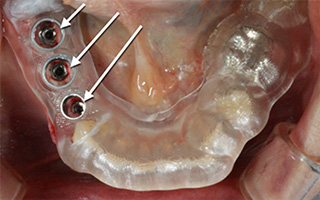

当院では、CTの3次元画像をもとに、インプラントの位置・方向・サイズをコンピューターでシュミレーションし、「設計図」を作成し、専門メーカー(Envista / ノーベルバイオケア社)に送信します。

メーカーから届けられた「サージカルガイ / ノーベルガイド」を手術時に口腔内にセットし、そのガイドにそってインプラントを埋め込むことで、手術の安全性と精密さを一層高めています。

この仕組みにより、均一で安定した結果を得ることが可能になり、安心して治療を受けて頂けます。当院では、2011年導入し、現在に至ります。

インプラントの被せ物はネジで装着、必要時は取り外し可能となります。

最終的にネジ穴は、白い樹脂で封鎖します。

上のネジ穴の写真やレントゲン画像から、インプラントが計画通りに埋入されて良好に終了していることが確認できます。